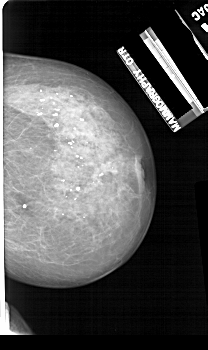

A_1114_1.LEFT_CC

LEFT_CC LINES 5146 PIXELS_PER_LINE 2866 BITS_PER_PIXEL 12 RESOLUTION 43.5 OVERLAY

FILE: A_1114_1.LEFT_CC.OVERLAY

TOTAL_ABNORMALITIES 1

ABNORMALITY 1

LESION_TYPE MASS SHAPE OVAL MARGINS SPICULATED

ASSESSMENT 4

SUBTLETY 3

PATHOLOGY MALIGNANT

TOTAL_OUTLINES 1

BOUNDARY